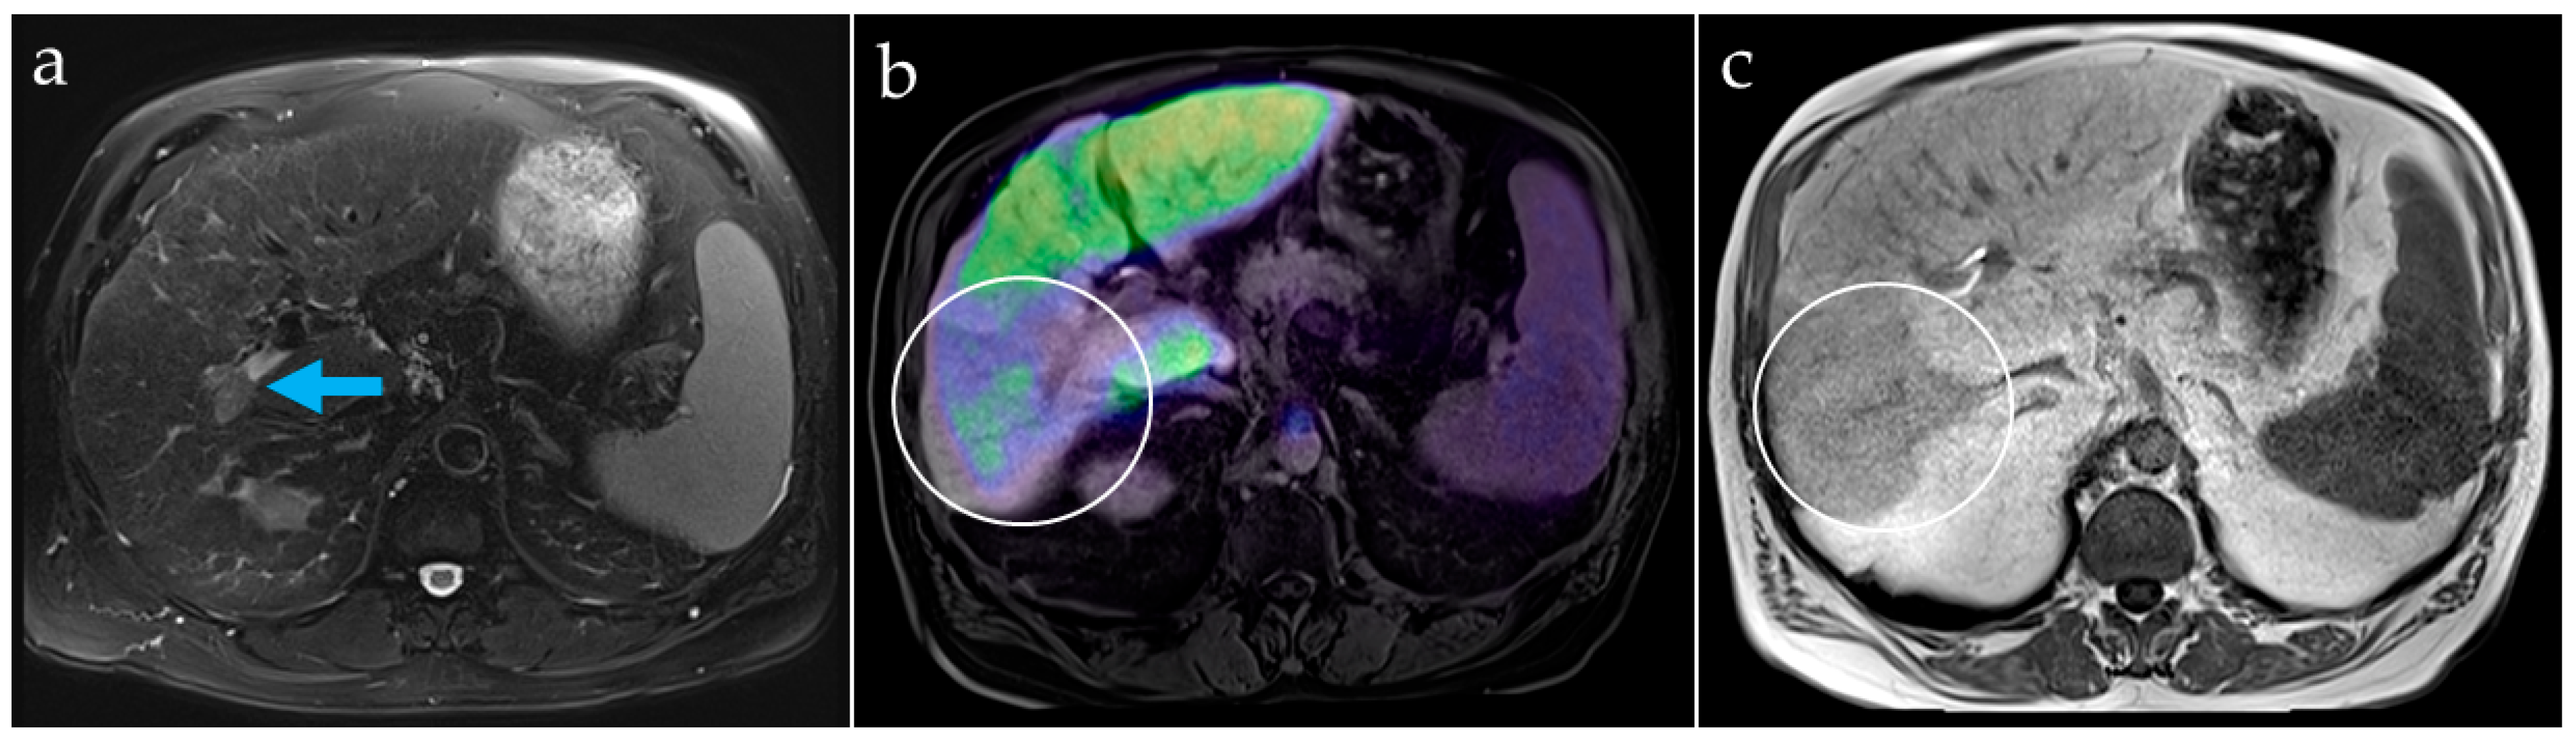

Figure 6. Patient B. Contrast-enhanced MRI of the liver in patient B shows tumor involvement and thrombus in the right portal vein branch ((a), arrow). The PET/MR fusion image (b) reveals liver areas with reduced [68Ga]Ga-BP-IDA uptake, corresponding to areas with liver texture disturbance on MRI (c), attributable to liver function impairment larger than the HCC lesions (white circles).

Patient B, also with newly diagnosed but partially necrotic HCC, showed homogenous hepatic uptake in the left liver lobe, but reduced uptake in liver segments V, VI, and VII, correlating with a changed signal in gadolinium-based contrasted MR imaging (Gd-EOB-DTPA, Primovist®, Bayer, Germany) that was attributed to a portal vein tumor thrombus and corresponding impairment of the tissue function (Figure 6). The tracer uptake in the non-tumorous, but cirrhotic liver tissue showed lower values than in patient A without liver cirrhosis, indicating impaired liver function (Table 1). Therefore, the tumor-to-liver ratio was lower. Gallbladder accumulation was seen early, after 10 min, suggesting sufficient biliary excretion.